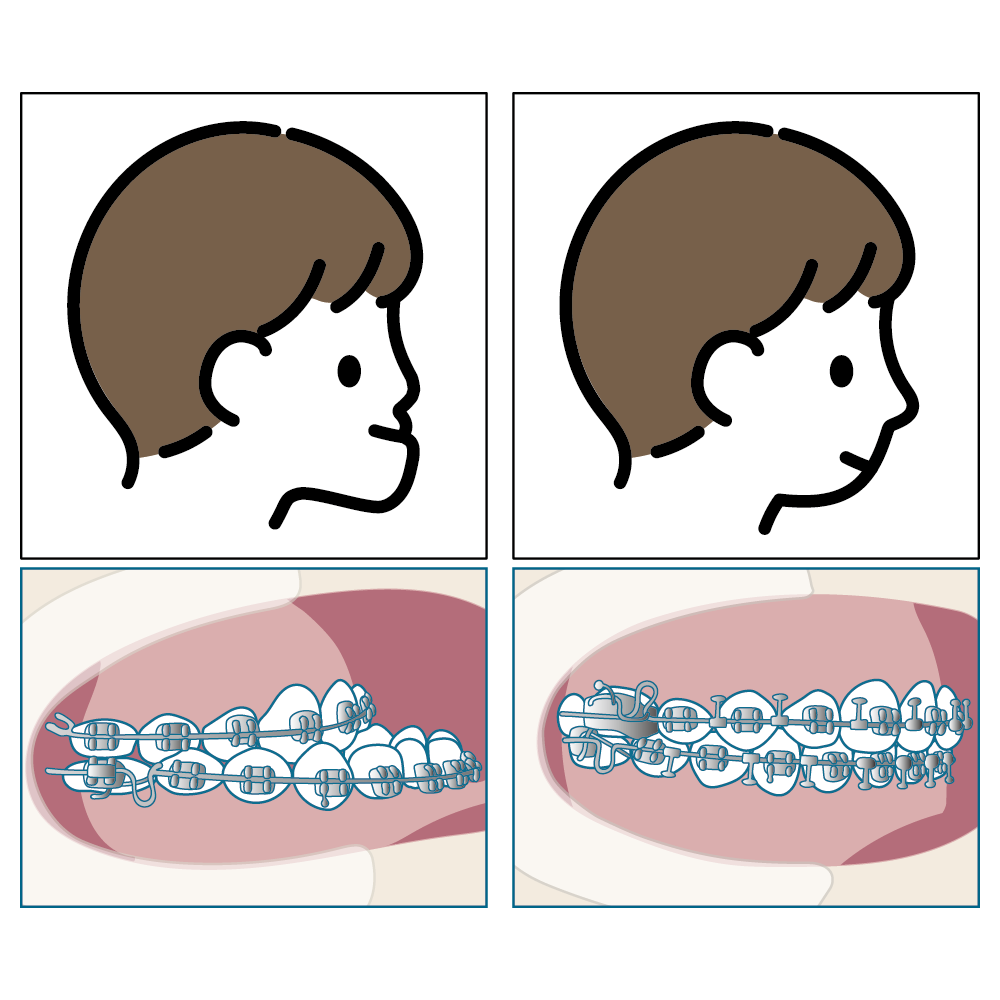

下あご自体が大きく前に出ている場合や、骨格の差が大きい場合は、外科手術(外科的矯正治療)が必要になることもあります。

- 矯正装置を使って歯並びを整える(術前矯正・矯正歯科)

- 顎の骨を切り、位置を調整する手術を行う(顎矯正手術・口腔外科)

- 術後に再度、矯正治療で微調整を行う(術後矯正・矯正歯科)

- 骨格的な問題を根本から改善できる

- 見た目の変化が大きく、横顔やフェイスラインも改善することが多い